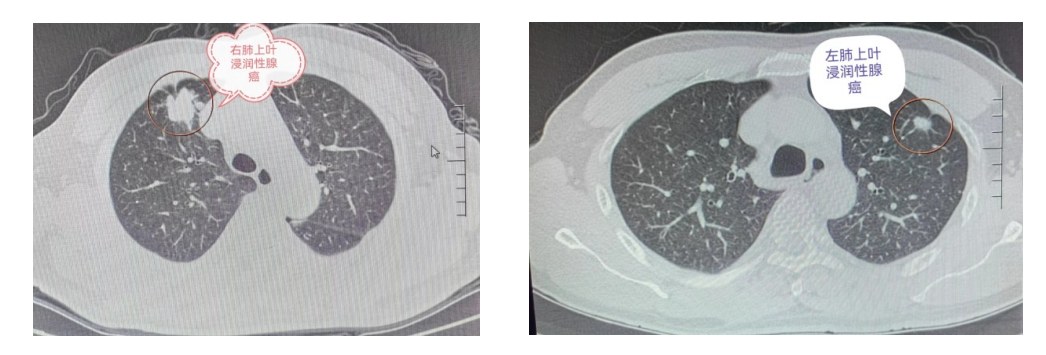

病例为一81岁晚期肺癌患者,去年4月因气喘胸痛入住在我院肺病科,胸部CT发现左肺上叶肿物(5.8cm×4.5cm)并左侧胸腔大量积液,经皮行肿物穿刺活检,病理与免疫组化明确为浸润性腺癌,综合评估诊断为左肺上叶浸润性腺癌并同侧肺门淋巴结、纵膈淋巴结及同侧胸腔转移,为晚期肺癌,无外科胸腔镜切除手术指征,穿刺肿瘤组织肺癌驱动基因为EGFR 21exon L858R突变,采用口服靶向药物+胸腔引流注药+肿块复合冷热消融微创减瘤术+中药综合治疗,治疗2个月患者症状明显改善,左肺上叶肿块明显缩小,消融后残留薄壁空洞,左侧胸腔残留少量积液,可以正常居家生活,每月至我院肺病科肺癌专病门诊取靶向药物维持治疗和定期复查胸部CT。今年4月复查胸部CT左肺上叶残留的薄壁空洞壁较去年12月增厚,结合该靶点口服药物治疗8个月至14个月容易出现耐药,综合评估为局部进展,依照目前中国和欧美国家相关肺癌诊疗指南,采用联合局部治疗的方案。 患者左肺上叶存在的癌性空洞,是热消融(射频、微波、激光)的禁忌症。方案一,向空洞内注入化疗药物,能杀灭内壁的肿瘤细胞,对外壁的肿瘤细胞无作用,达不到预期的临床效果。方案二,采用经皮复合冷热消融术,但常规冷冻消融因空气的传导特性,达不到灭活空洞壁的肿瘤细胞效果。方案三,使用同轴引导针,注入自体靜脉血,血凝块充填空洞,再从同轴置入复合冷热消融针,便可以高效率传导冷源灭活肿瘤细胞的临床预期治疗效果。微创消融过程顺利,一针两用,为患者节省了1万多元,患者术后半天下床行走,第三天出院。 「肺结节与肺癌」 肺结节是指影像学表现为肺内直径≤3cm的局灶性、类圆形或不规则形病灶,影像学表现为密度增高的阴影,可单发或多发,边界清晰或不清晰的病灶。依据大小分类:<5 mm定义为微小结节;5-10 mm定义为小结节;>10 mm的结节需尽早诊治。依据结节密度分类:实性肺结节、磨玻璃密度结节和部分实性结节。恶性概率:部分实性结节>磨玻璃密度结节>实性结节。不同性质的结节有不同的风险评估与处理策略。 「晚期肺癌不是绝望」 由于缺乏对肺癌的防护与早筛早诊意识,大部分肺癌在确诊时,已是中晚期及晚期,错过了早期根治的机会。目前肺癌的治疗早已经进入精准治疗、多学科、多模态诊疗的时代,通过综合治疗,明显提高晚期肺癌患者的生存质量,延长生存时间,带“瘤”生存,随着新型药物和设备的不断研发、生产及临床应用,肺癌终将成为一种慢性疾病。 肺病科(肺部肿瘤专科)肺结节、肺癌专病门诊:阳春市中医院中西医6号诊室